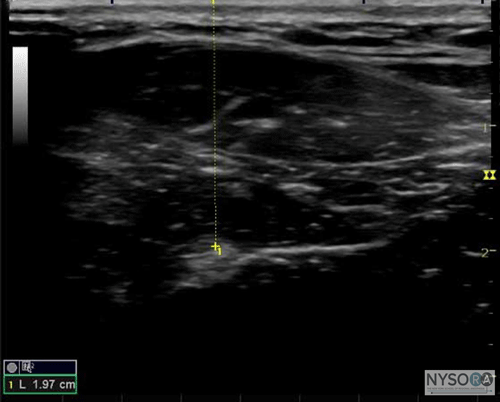

More recently, a study was conducted on 55 patients scheduled for upper limb surgery who received ultrasound guided supraclavicular brachial plexus blocks. The authors set out to determine the minimum current threshold for motor response both inside and outside the first trunk encountered. (11) They discovered that the median minimum stimulation threshold was 0.60 mA outside the nerve and 0.3 mA inside the nerve. Interestingly, stimulation currents of ≤0.2 mA were not observed outside the nerve, whereas 36% of patients experienced a twitch at currents Taken together, these data suggest that although the sensitivity of a "low-current" twitch for intraneural placement is not high, the specificity is. Put another way, the needle tip can be in the nerve and not elicit a motor response at very low currents; however, if a twitch is elicited at Most regional anesthesiologists agree that injection of local anesthetic into the nerve may be a risk factor for injury and that extra-neural deposition minimizes the potential for an intrafascicular injection. (12) Ultrasonography is good, but not perfect, at delineating the exact position of the needle tip. In our attempts to get "close, but not too close" to the nerve so we might have the best block result, needles occasionally but inevitably cross the epineurium into the substance of the nerve. This event in and of itself may be of minimal consequence. (13) However, injection into a fascicle carries a high risk of injury. (14) It is for this reason that a reliable electrical monitor of needle tip position is a useful safety instrument. If a motor twitch is elicited at currents Overall, nerve stimulation adds little to the cost of a nerve block procedure, in terms of time, clinician effort, or dollars. It also serves as a useful functional confirmation of the anatomic image shown on the ultrasound screen (e.g. "Is that the median or ulnar nerve?"). In our practice, nerve stimulator is routinely used in conjunction with ultrasound guidance as an invaluable monitor of the needle tip position with respect to the nerve, based on the association of low currents with intraneural placement. In addition, an unexpected motor response during ultrasound-guided blocks may alert the operator of the needle-nerve relationship that was missed on ultrasound. Ultrasonography The use of ultrasound guidance to assist in nerve block placement has become very popular, for a number of reasons. First, ultrasound allows visualization of the needle in real time and therefore quickly and accurately guide the needle toward the target. Multiple injection techniques that were difficult, or indeed dangerous, to do in the era of nerve stimulation alone are now easy to perform because the nerves can be seen and injectate carefully deposited at various points around them. Also, because a motor response is not technically required, blocks can now be performed in amputees who do not have a limb to twitch. Not surprisingly, ultrasound has the potential to improve the safety of peripheral nerve blocks for a number of reasons. First, adjacent structures of importance can be seen and avoided. The resurgence in popularity of the supraclavicular block is a testament to this. Before ultrasound, the highly effective block was relatively unpopular as a means of anesthetizing the brachial plexus, for fear of causing a pneumothorax, despite the paucity of data regarding its actual incidence. However, now that the brachial plexus and, more importantly, the rib, pleura, and subclavian artery can all be seen at the supraclavicular level, this block has become common in clinical practice. However, recent reports of pneumothoraces serve as a reminder that while ultrasound may reduce the incidence of complications of nerve blocks, it is unlikely to entirely prevent when used as a sole monitor. (15,16) Similarly, there are reports of intravascular and intraneural needle placement witnessed (and despite the use of) ultrasound, highlighting the need to use care with this technology that is, in the end, a tool that is not failsafe. (17-19) A useful adjunct to the visualization of structures on the ultrasound screen is the ability to measure the distance from skin to target using electronic calipers (Figure 2). This, coupled with needles that have depth markings etched on the side of the nerve block needles, confers a great safety advantage by warning the clinician of a "stop distance," or a depth beyond which he or she should stop, reassess the needle visualization, and perhaps withdraw and begin again. Another important advantage that ultrasound can confer is the ability to see the local anesthetic distribution on the screen image (Figure 3). If corresponding tissue expansion is not seen when injection begins, then the needle tip is not where it is thought to be, and the clinician should immediately halt injection and relocate the tip of the needle. This is particularly worrisome in vascular areas because the lack of spread can signal the intravascular needle placement. However, ultrasound has been used successfully to diagnose an intra-arterial needle tip placement when an echogenic "blush" was noted in the lumen of the artery, allowing for rapid cessation of the block technique and avoidance of what surely would have been systemic toxicity. (20,21) ![]() Figure 2: An example of ultrasound being used to determine the depth of a structure of interest. Similarly, ultrasound may also be able to reduce the likelihood of systemic toxicity by allowing clinicians to use less local anesthetic. Several authors have published large reductions in the volume required to affect an equivalent block to standard nerve stimulation techniques. For example, Casati et al demonstrated a significant reduction in volume required to produce an effective three-in-one block (22 mL vs. 41 mL). (22) Sandhu et al showed in a feasibility study that infraclavicular block was possible using ultrasound with volumes typically half of what were used with nerve stimulation alone (16.1 ± 1.9 mL). (23) Riazi et al published a study in 2008 showing that ultrasound guidance allowed for a substantial reduction of volume for interscalene block used for postoperative pain while still providing a quality block (5 mL vs. 20 mL). (24) Interestingly, this low dose also resulted in less diaphragmatic impairment related to phrenic nerve paresis. The utility of ultrasound in prevention of nerve injury during peripheral nerve blockade is likely over-estimated. The problem is threefold: First observing the needle tip in relation to the nerve is user dependent, and one can often be fooled by poor technique or simply unfavorable echogenic characteristics of the tissue-needle interface; second, the current resolution available is not adequate to distinguish between an intraversus extrafascicular needle tip location. This difference is crucial because evidence is mounting that an intraneural (but extrafascicular) injection is likely not associated with injury, whereas injection inside the fascicles themselves produces clinical and histologic damage. (14,25) Lastly, once injection has begun, even a minuscule amount of local anesthetic can produce damage if intrafascicular. (26) Relying on the visual confirmation of tissue expansion may result in damage before expansion is detected on the screen. It is, in other words, probably too late.